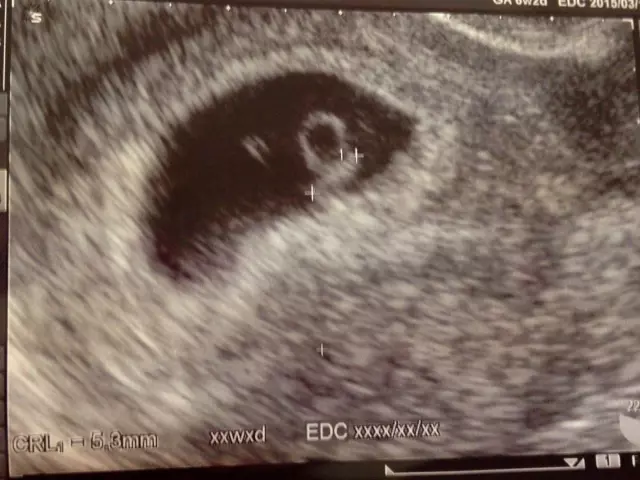

妊娠が成立すると、まず子宮内に「胎囊」と呼ばれる袋状の構造が確認できるようになります。胎囊は、受精卵が子宮内膜に着床した後に形成され、超音波検査では妊娠4〜5週頃から黒い楕円形の袋として映し出されます。妊娠のごく初期に確認されるもっとも基本的な所見であり、妊娠が順調に進んでいるかどうかを判断するための最初の目安となります。

胎囊は妊娠週数に応じて少しずつ大きくなり、妊娠6週頃には胎芽が確認されるようになります。さらにその後、心拍が観察できれば、妊娠が継続していることを強く示す重要なサインとなります。一般的に、胎囊は妊娠週数+10mm前後の大きさで発育するのが標準とされており、この増大のペースが妊娠経過を評価する大きな指標となります。

胎囊の大きさは「GS(Gestational Sac)」という指標で測定され、**胎囊の最大径(mm)**をもとに評価されます。以下は一般的な妊娠週数ごとの胎囊サイズの目安です。

| 妊娠週数 | 胎囊の大きさ(平均値) |

| 4週0日〜4週6日 | 約2〜10mm |

| 5週0日〜5週6日 | 約10〜20mm |

| 6週0日〜6週6日 | 約20〜30mm |

| 7週0日〜7週6日 | 約30〜40mm |

※あくまで平均的な目安であり、多少の個人差はあります。

胎囊の大きさと胎芽の確認時期

胎囊の大きさが20mm程度になると、多くの場合で胎芽が確認されます。胎芽が見えた後は、心拍の有無が重要な指標となり、妊娠が順調に進行しているかを判断します。